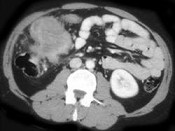

- 单项选择题男,42岁, 左下腹可触及一长条形肿块,结合图像, 最可能的诊断是 ( )

A、结肠间质瘤

B、结肠转移癌

C、结肠淋巴瘤

D、假膜性肠炎

E、结肠癌